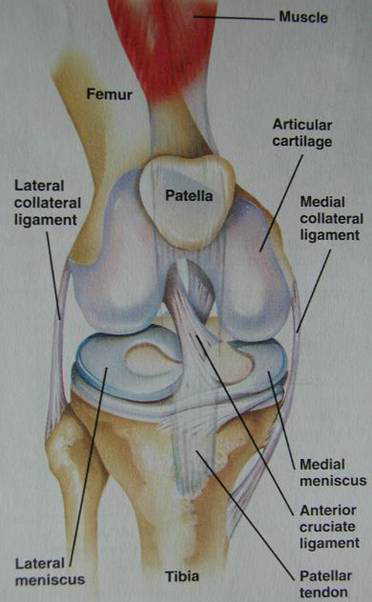

半月板的解剖

內(nèi)側(cè)半月板后角既寬大又活動度小,最易受傷。

半月板血液供應

邊緣處和前后角(10-30%)

半月板的寬高度

v寬11-12mm,所以超過3個層面的前后角相連就可能是盤狀;

v最高處約10-11mm,所以高度大于15mm的半月板是盤狀